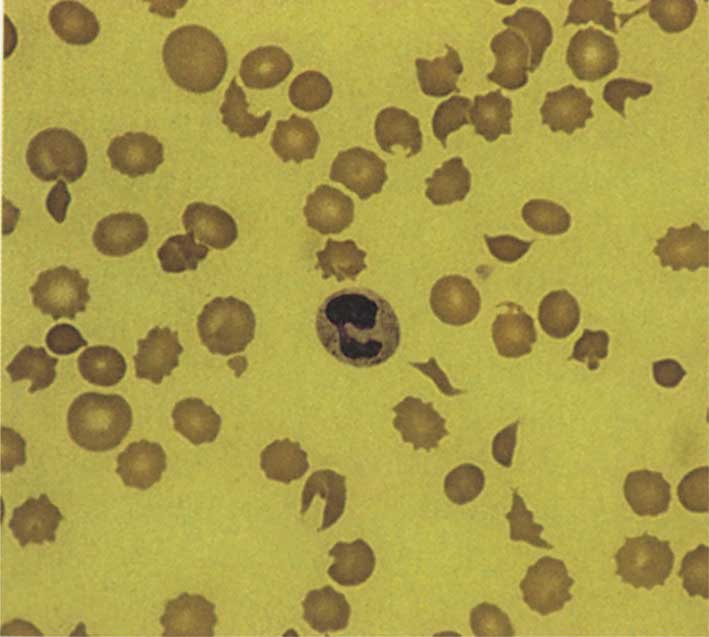

للطاخة المحيطية شأن كبير في تقيييم الكريات الحمر، فعليها يمكن مشاهدة اختلاف شكل الكريات poikilocytosis مثل الكرية المجزأة أو الخوذية كما في الشكل، كما يمكن معرفة وجود اختلاف الحجم anisocytosis كالكريات الكبيرة (< 10مكرون) أو الصغيرة (أقل من 5 مكرون)، وينسب حجم الكريات الحمر عادة إلى نواة الكرية اللمفاوية السوية (الشكل1)، يمكن كذلك تعرف الكريات المكورة spherocytes والمنجلية والهدفية وغيرها.

وتفيد اللطاخة في دراسة صباغ الكريات، وهنا لابد من التطرق إلى شكل الكرية الحمراء فهي بشكل القرص كما هو مبين في الشكل، وتبدو على اللطاخة بشكل حلقة قاتمة في المحيط ونيرة في المركز بنسبة الثلث تقريباً؛ وزيادة المركز النير يدل على نقص الصباغ، كذلك فإن بعض الاضطرابات المرضية قد تصيب الكريات الحمر ويستدل من خلالها على نوع المرض مثل الترقطات الأسسة المشاهدة في التسمم بالرصاص، أو أجسام هاول جولي المشاهدة بعد استئصال الطحال، أو أجسام هاينز في عوز G6PD.